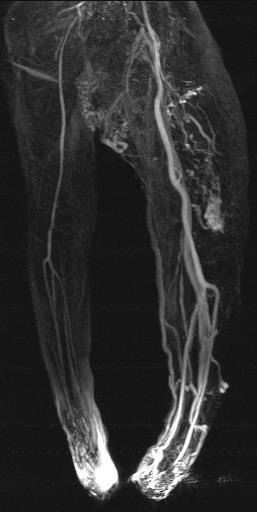

♀, 3 ys, Parkes-Weber-Syndrom

Parkes-Weber |

+ |

CAVM,CLAVM |

1900年Klippe和Trenaunay两名医师首先报道此征,描述它有3个主要临床表现:①血管瘤;②软组织和骨质增生,病肢增粗和过长;③浅静脉曲张。1918年Parkes-Weber又报道另一种肢体先天性疾病,除了上述3个主要症状外,还有动静脉瘘存在,被称为Parkes-Weber综合征(简称PWS),限于当时诊断水平,由于KTS的临床表现与PWS以及其他一些血管瘤病变有较多相似之处,造成对KTS认识混淆。 |